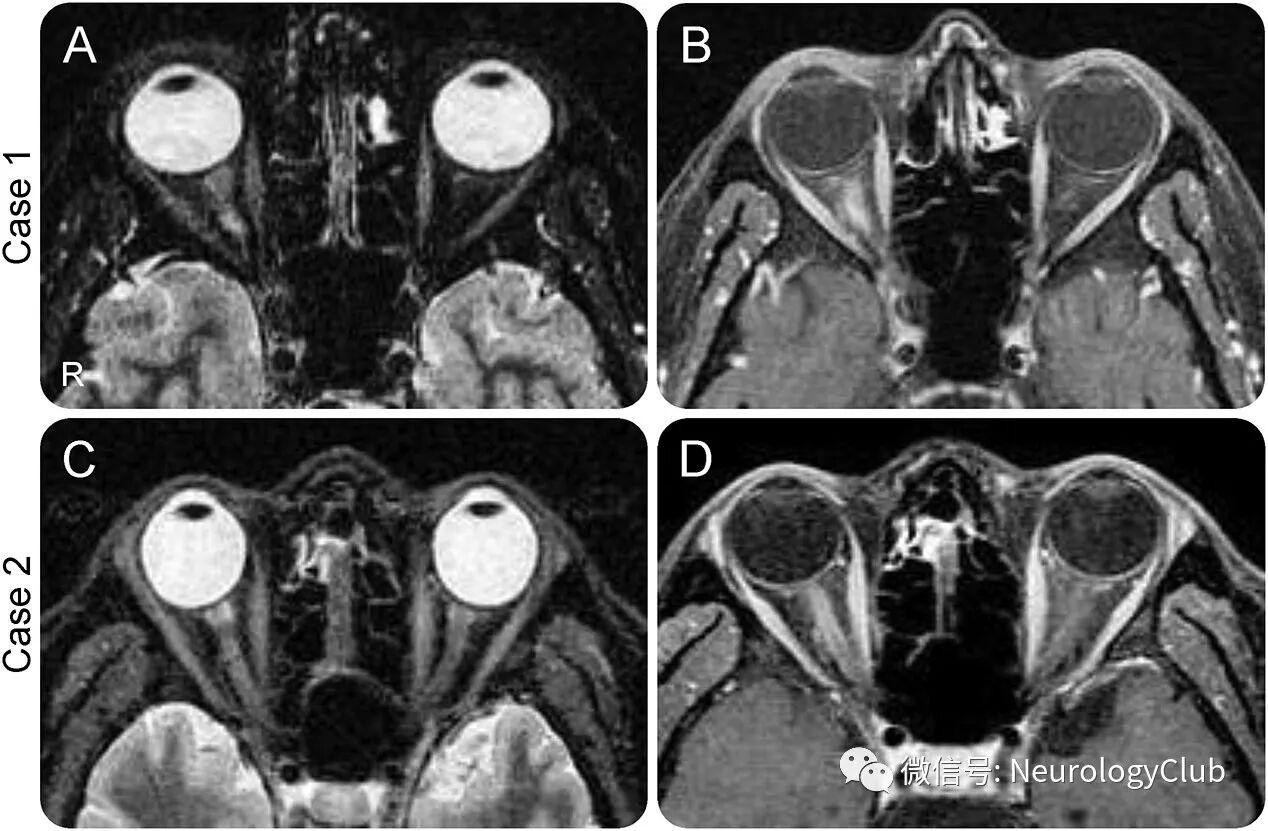

除了病例1外,还发现3例血清MOG抗体阳性的病例。4例患者的临床特征见表1。所有患者均为男性,平均发病年龄为34岁(23-39岁)。均有癫痫发作,3例出现行为异常,2例出现ON(图1),1例出现排尿困难,没有患者存在脊髓病变。脑脊液(CSF)检查平均细胞数为83/μL(平均为29-311/μL),平均蛋白浓度为46mg/dL(35-86mg/dL)。3例(病例1-3)患者的CSF行MOG抗体检测,结果均阳性,但无髓鞘碱性蛋白(Myelin basic protein,MBP)增加。4例患者均行头颅MRI检查,FLAIR上可见单侧大脑皮质高信号病灶(图2-3)。本组研究中其他MOG抗体阴性的病例均未出现如上的MRI改变。4例患者接受静脉注射大剂量糖皮质激素并给予抗癫痫药物治疗后完全恢复。同时检测了其它脑炎相关的抗体(AQP4、NMDAR、AMPA、LGI1、CASPR2、GABAb),但结果均为阴性。

(图1:A、C:短T1反转恢复序列;B、D:增强序列;病例1和2可见右侧视神经高信号病灶伴强化,提示单侧视神经炎)